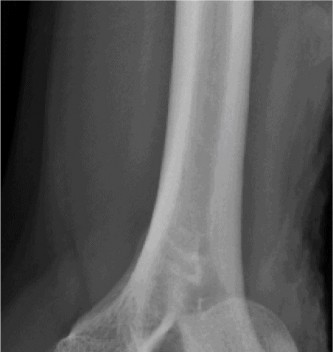

A 54-year-old male presented to the ED with left elbow pain after sustaining an injury in a low speed motor vehicle accident. He denied any other injuries. On examination, he had no open injuries and was neurovascularly intact. He had gross deformity about the elbow. His images are below (Figs. 2–89 to 2–92).

Figure 2–91 Pre- and post-reduction films showing complex elbow dislocation, coronoid fracture.

The correct answer is (C). Posteromedial complex elbow dislocation. This injury is proposed to result from axial load combined with posteromedial rotation, varus force, and elbow flexion. This is opposed to the more frequently seen posterolateral dislocation. There is a fracture of the coronoid, which is typical for this type of injury.

The correct answer is (A). Coronoid process fracture (see Fig. 2–93). The medial trochlea is thought to fracture the anteromedial facet of the coronoid allowing the elbow to dislocate. The lateral collateral ligament (LCL) ligamentous complex is also torn with this type of injury however the radial head often remains intact. This is in contrast to posterolateral elbow dislocations in which the radial head is the most commonly fractured bone, followed by the coronoid.